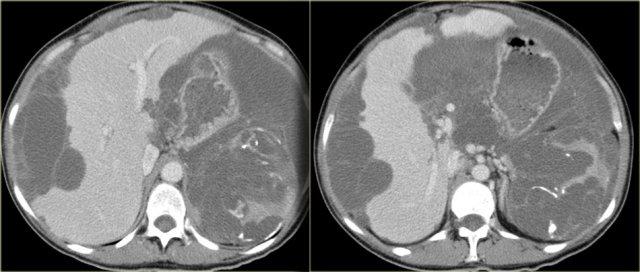

Giả u nhầy phúc mạc với hình ảnh lõm múi rõ rệt trên bề mặt gan và gần như phá hủy lách. Lưu ý các vôi hóa

Đặc điểm điển hình của giả u nhầy phúc mạc là hình ảnh lõm múi trên bề mặt gan và lách.

Khác với di căn phúc mạc, không có các nốt khối u.

Có thể có một số vôi hóa.

Bên trái là một trường hợp giả u nhầy phúc mạc khác.

Hầu như không có hình ảnh lõm múi trên bề mặt gan.

Lưu ý dây chằng liềm dày lên.

Có nang nhầy của ruột thừa (mũi tên).

Dấu hiệu này hiếm khi được ghi nhận.